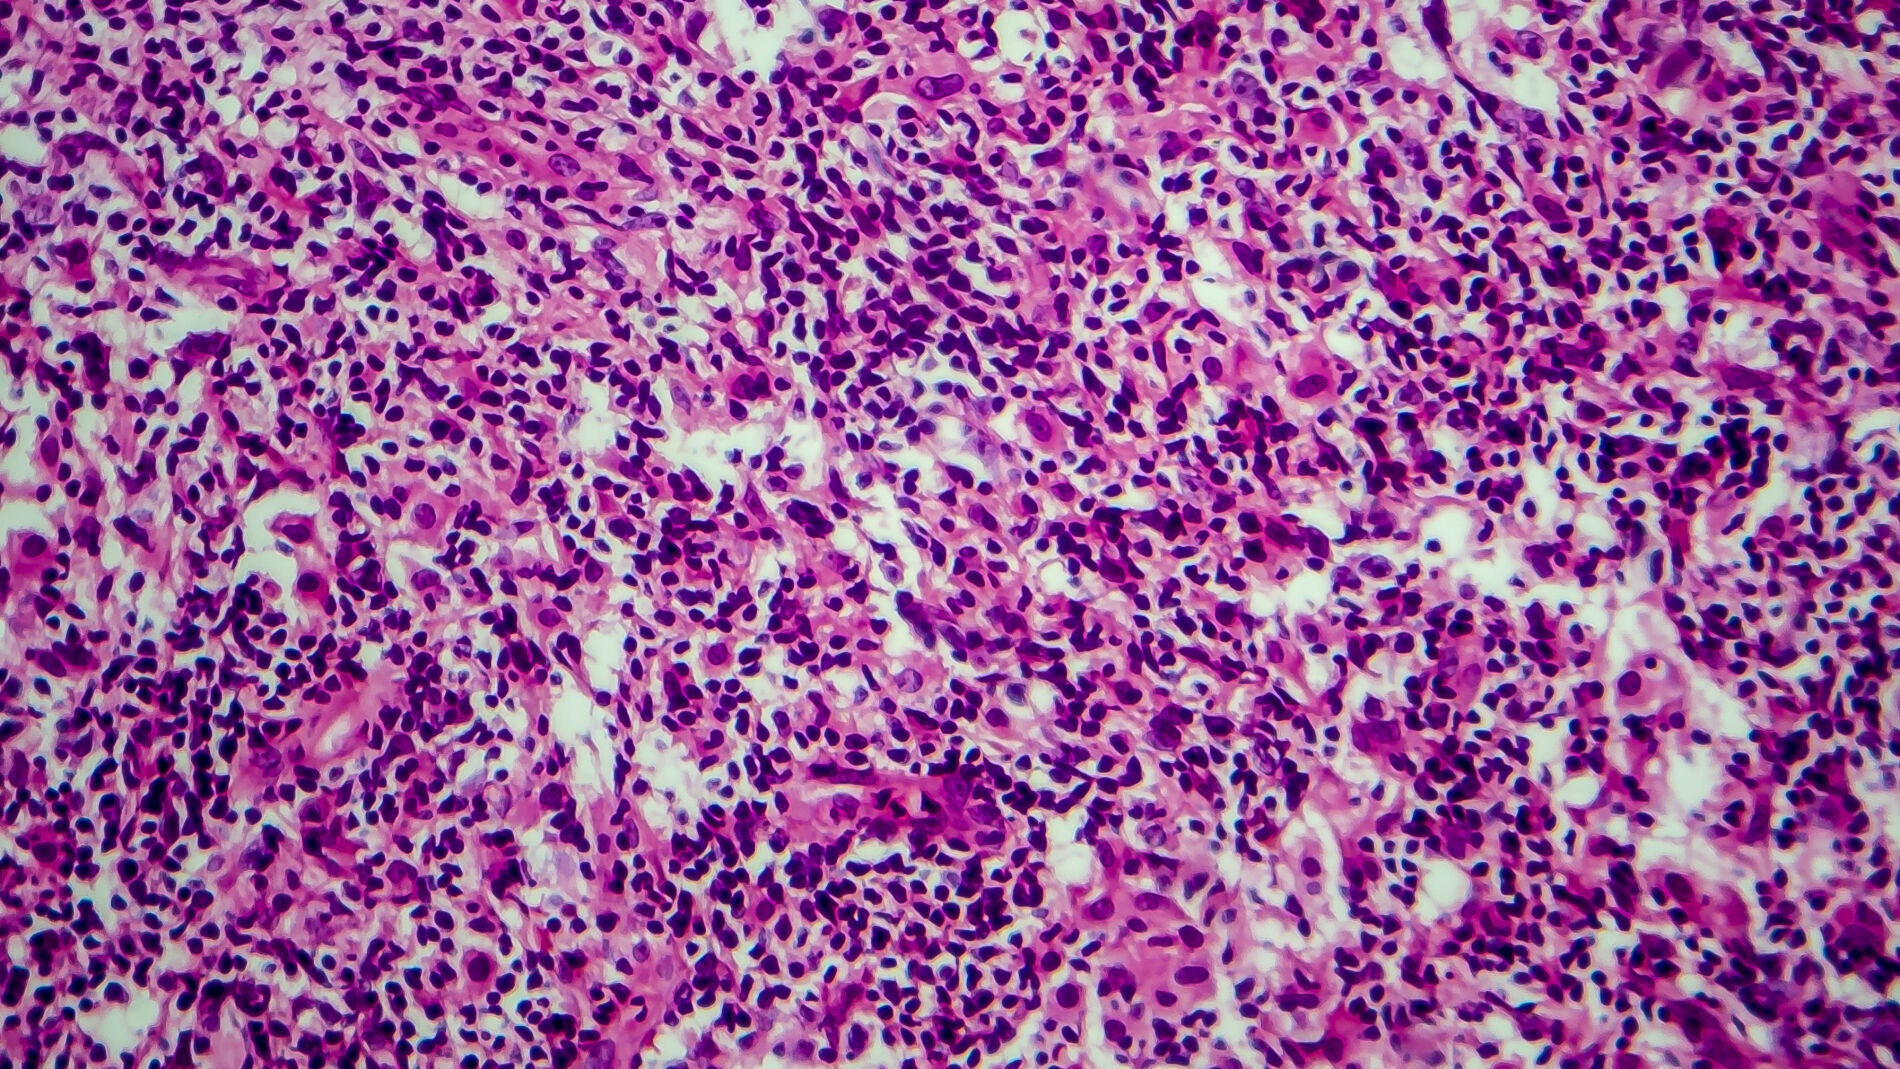

A partir del 1 de abril estará disponible la terapia liso-cel para adultos, un tratamiento que ha demostrado una remisión completa del 75% y del 95% en el caso del linfoma difuso de células B grandes y en el linfoma folicular, respectivamente...